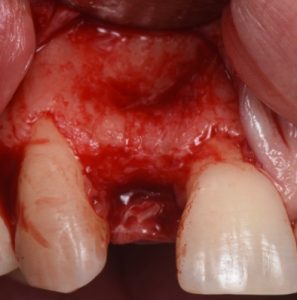

The procedure is presented step by step, including flap design and management, defect assessment, membrane selection and stabilization, flap advancement, and suturing techniques. Emphasis is placed on achieving tension-free closure and maintaining hard and soft tissue contours critical for esthetic success.

- Criteria for choosing staged GBR versus simultaneous implant placement

- Flap design principles in esthetic-zone defects